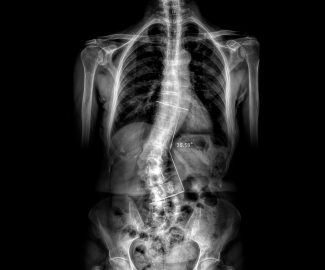

Sabemos que visitar un centro médico a veces genera nervios. Por eso, hemos creado un ambiente cálido, moderno y 100% seguro para ti. Desde nuestra cómoda sala de espera hasta nuestras áreas de ecografía, mamografía y rayos X, cada rincón está equipado con tecnología de última generación y diseñado para que te sientas en confianza.